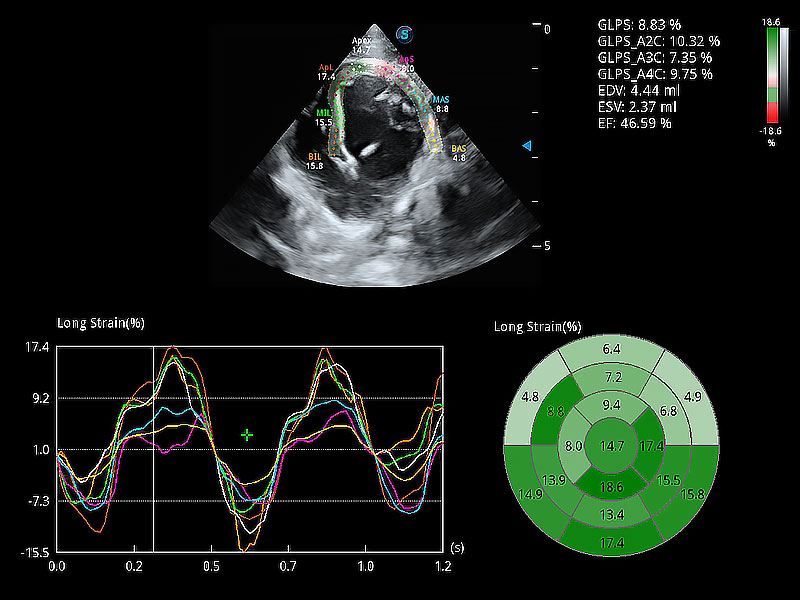

通過(guò)心肌識(shí)別技術(shù)與二維斑點(diǎn)追蹤技術(shù)相結(jié)合,對(duì)心臟的超聲圖像進(jìn)行量化分析。計(jì)算心肌17個(gè)節(jié)段的應(yīng)變、應(yīng)變率、速度、位移等,并通過(guò)牛眼圖的形式進(jìn)行呈現(xiàn)。